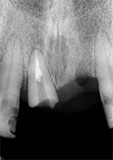

antes depois